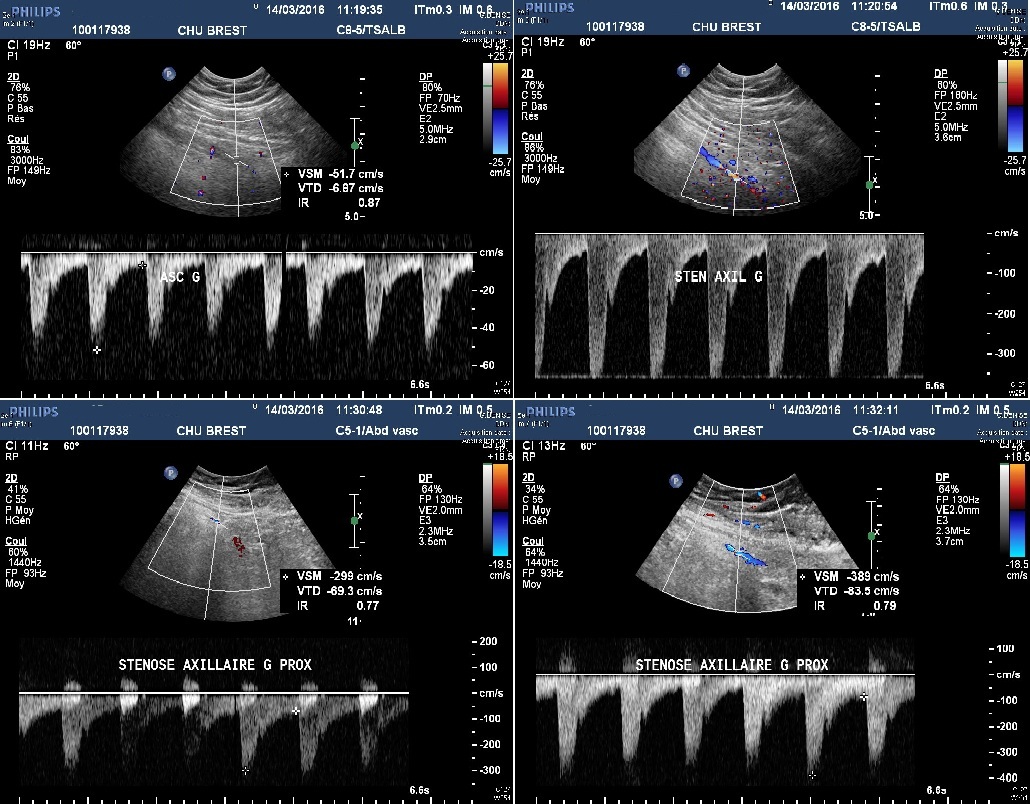

Sténose de l'artère axilaire gauche dans le cadre d'une artérite à cellules géantes